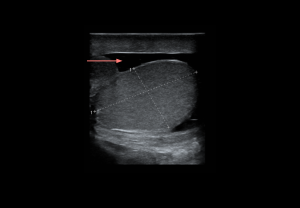

Traumatic Disorders

Testicular trauma

Extratesticular lesions

- Hydrocele: anechoic fluid between tunica vaginalis layers; no Doppler flow.

- Hematocele: heterogeneous fluid collection with echogenicity varying by chronicity; no internal flow. Large collections may reduce testicular perfusion by compression.

Intra-/extratesticular lesions

- Hematoma: well-defined avascular lesion; echogenic in the acute phase, hypoechoic in the chronic phase.

Intratesticular lesions

Integrity of the tunica albuginea determines management:

- Testicular fracture: Intact tunica albuginea, linear hypoechoic band, preserved peripheral flow.

- Testicular rupture: Disrupted tunica albuginea with parenchymal extrusion, heterogeneous echotexture, absent/reduced flow.